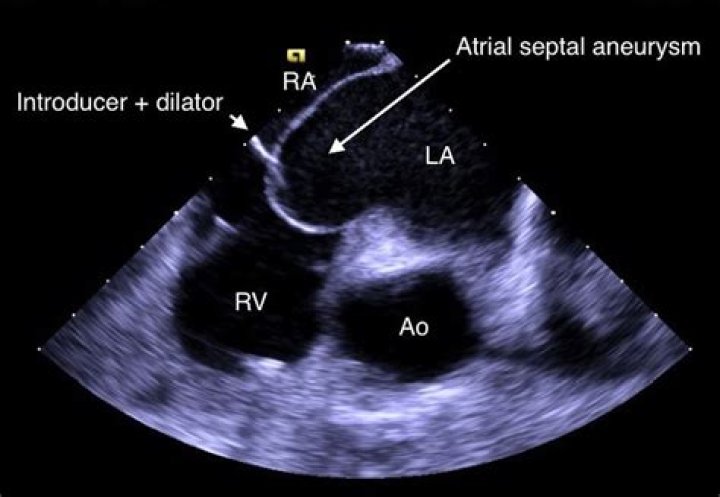

The interatrial septum is the thin wall that separates the upper atrial cavities of heart. When it appears elongated and “floppy” on cardiac ultrasound, we call it “aneurysmal”. This is a condition that some people are born with. It alone portends no prognostic risk.

Introduction. Atrial septal aneurysm (ASA) is a congenital deformity of interatrial septum consisting redundant and mobile interatrial septal tissue in the region of fossa ovalis with bulging into the right or left atrium and sometimes oscillating between both atria.

It is a localized bulging of the inter-atrial septum into either or both atria during the cardiac cycle. ASA has been reported as an unexpected finding during autopsy but may also be diagnosed in living patients by echocardiographic techniques...